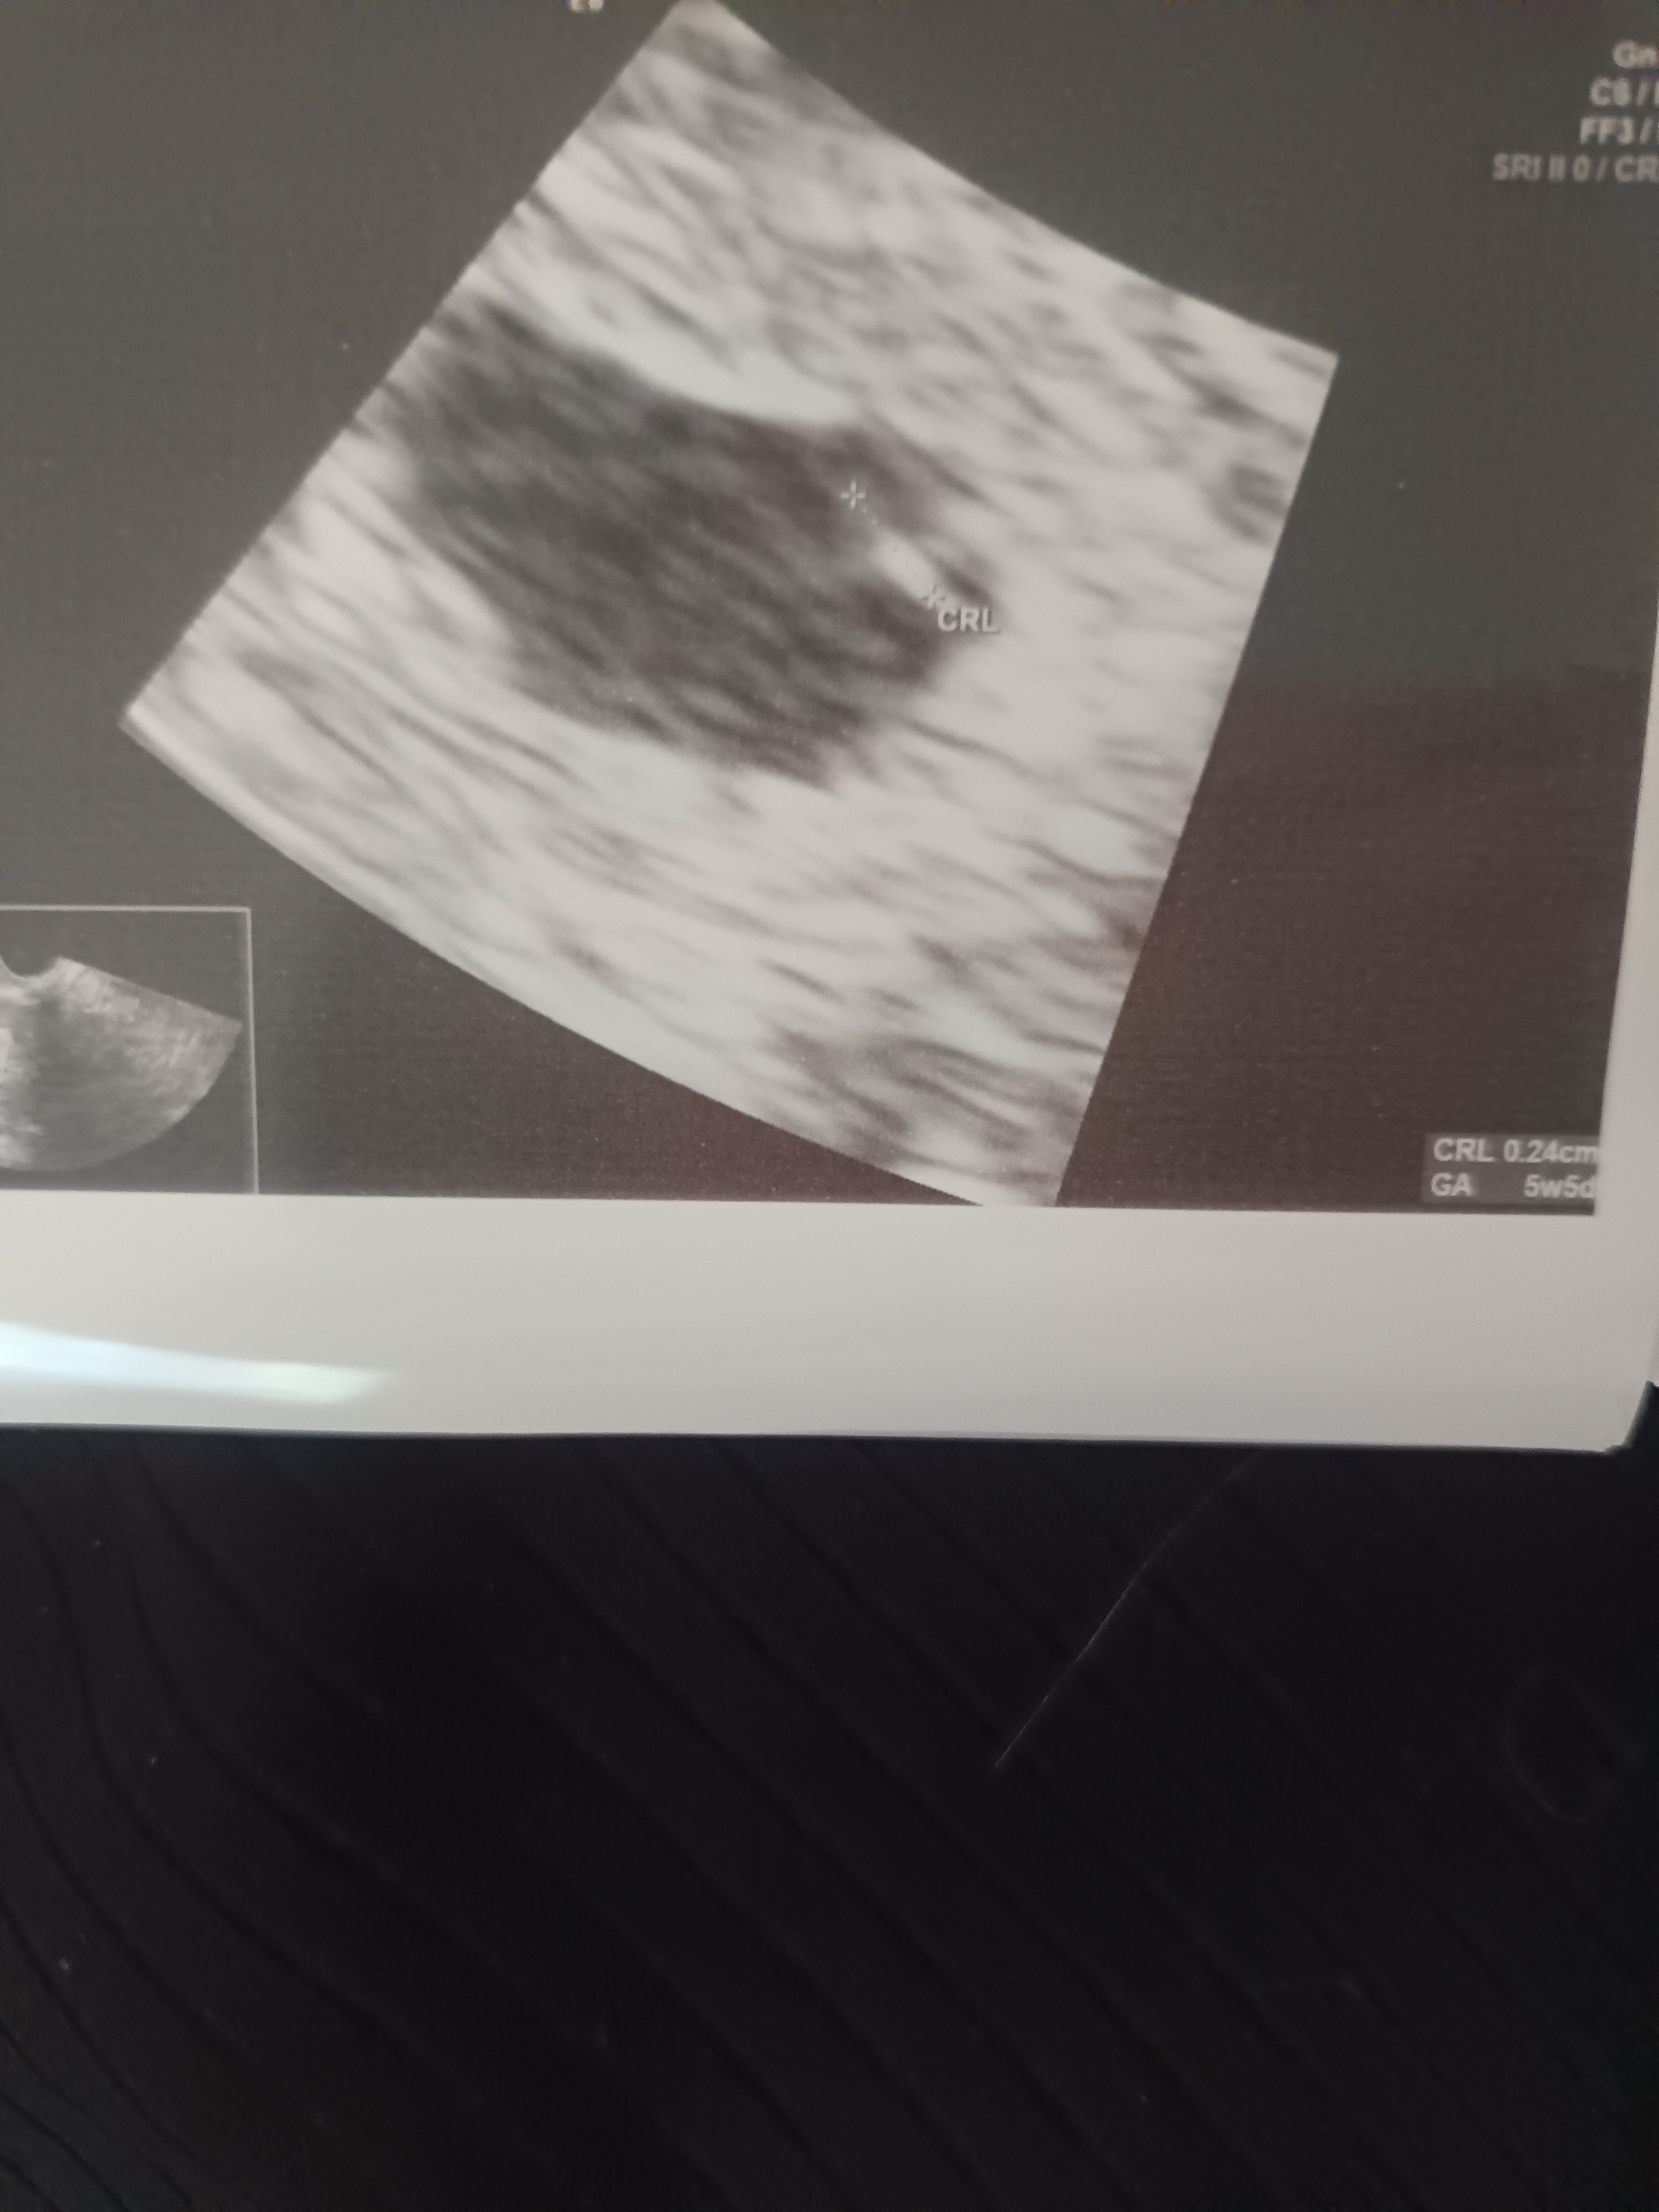

Witamy się w dwupaku

Termin pokrywa się z USG

. 2maj 2026

Nasz kropek![]()

CudownieDzień dobry .

. 2maj 2026![]()